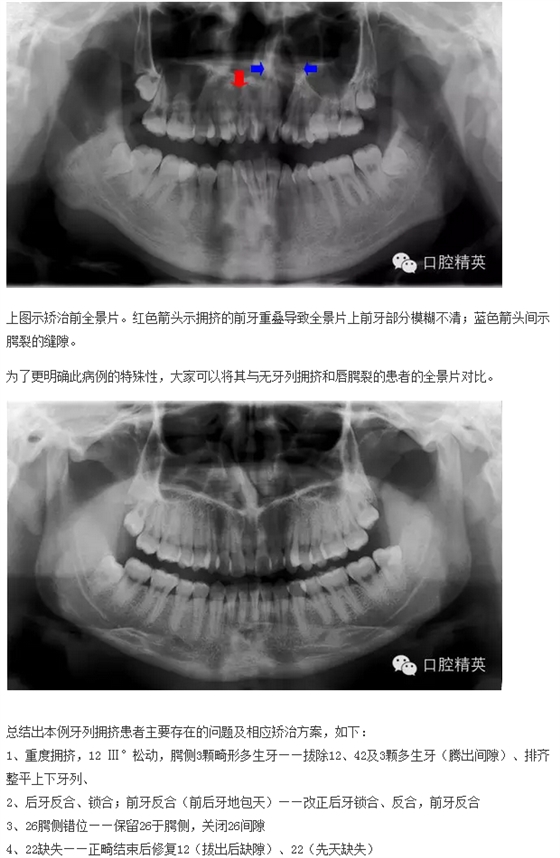

下面來(lái)個(gè)圖,震撼一下大家的心靈。

來(lái)源于口腔精英